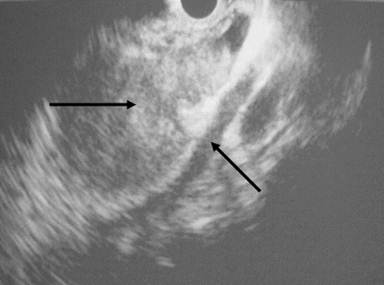

A 38-year-old woman with no previous surgical history presented with epigastric abdominal pain. Ultrasound examination and a computed tomography (CT) scan showed a 4 cm heterogeneous lesion in the pancreatic body. This tumor invaded the splenic artery and vein (Figure 1). No lymph node extension was noted. Endoscopic ultrasound-guided (Figure 2) fine-needle biopsy confirmed a neuroendocrine tumor. Biologic tests regarding the suspicion of a functional neuroendocrine tumor were normal. The patient was referred for surgical treatment.

Figure 2. Pancreatic tumor and the splenic vein (endoscopic ultrasound). |